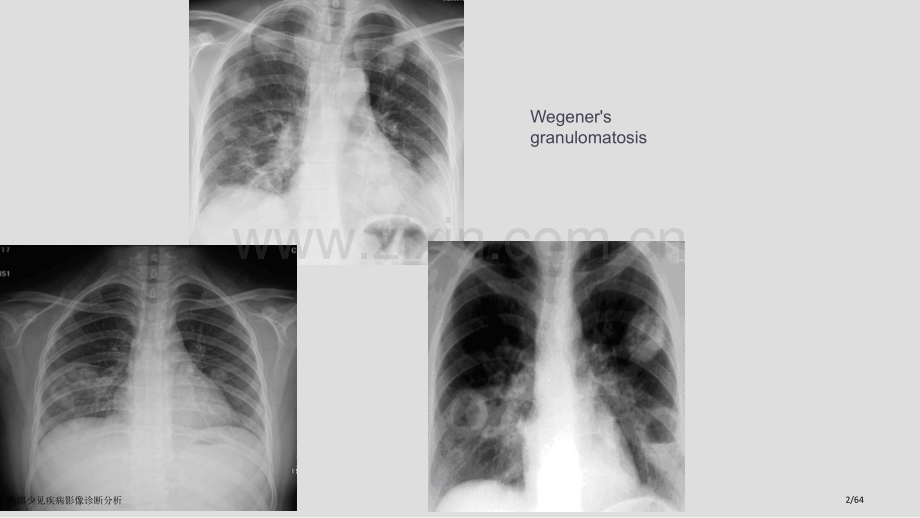

胸部少见疾病影像诊疗胸部少见疾病影像诊断分析1/64Wegenersgranulomatosis胸部少见疾病影像诊断分析2/64WEGERGRANULOMA胸部少见疾病影像诊断分析3/64Wegenersgranulomatosis胸部少见疾病影像诊断分析4/64肺肺WegenerWegener肉芽肿肉芽肿CT表现:(1)两肺多发结节,少数可单发,大小可数毫米到数厘米不等,边缘光滑或稍含糊;(2)约二分之一病灶有空洞,多为内壁一规则厚壁空洞,病灶发展时空洞增大,空洞壁可变薄,甚至可见液平面,巨大空洞可达整个肺叶。经治疗后随病情好转空洞缩小,甚至完全消失;(3)可见小点状钙化,多出现于长久治疗后,且主要位于肿块边缘;(4)邻近支气管扩张及囊泡状肺气肿;(5)周围可见毛刺及胸膜凹陷征;(6)纵隔淋巴结肿大用胸腔积液少见。胸部少见疾病影像诊断分析5/64Godman提出WG必须满足三个条件:上呼吸道坏死性肉芽肿病变、血管炎上呼吸道坏死性肉芽肿病变、血管炎及肾小球肾炎及肾小球肾炎(即威格纳三联征),近年增加了cANCA阳性。ANCA为抗中性粒细胞胞浆本身抗体,抗体滴度与疾病活动程度相关并可预测疾病是否复发。胸部少见疾病影像诊断分析6/64肺淋巴管平滑肌瘤病肺淋巴管平滑肌瘤病(PLAM)基本病理特征是淋巴管、小血管、小气管管壁及其周围类平滑肌细胞进行性增生,呈错构瘤样改变,使气管局限狭窄而形成空气潴留,使远端肺泡扩大融合呈囊状腔,胸膜下囊腔破裂可造成气胸;当淋巴管或胸导管阻塞可引发淋巴回流障碍甚至形成乳糜胸、腹水;肺小静脉远端管腔内瘀血扩张甚至破裂出血,引发患者咯血。胸部少见疾病影像诊断分析7/64胸部少见疾病影像诊断分析8/64PLAM女31胸水胸部少见疾病影像诊断分析9/64肺淋巴管平滑肌瘤病肺淋巴管平滑肌瘤病CT表现 本病特征性CT表现是肺内小气囊。囊变型病变表现为双肺弥漫分布小气囊,边界清楚不规则线样壁。大多数气囊呈圆形,少数小叶间隔壁呈多角型形,局部见多个气囊相重合。平滑肌细胞型病变表现为线样密度灶和局部肺区毛玻璃样密度。后期并并发症以气胸较为常见发症以气胸较为常见,有少许胸水,并可见有淋巴结肿大。少数患者CT检验可发觉肾血管平滑肌瘤。胸部少见疾病影像诊断分析10/64PLAM影像学上可见双肺弥漫囊状影,囊状影分布无部位差异。囊壁厚度多小于2mm,血管影多位于囊壁边缘。囊状影之间为相对正常肺组织囊状影之间为相对正常肺组织,极少融合60%患者出现乳糜胸水,患者出现乳糜胸水,40%合并气胸。合并气胸。本病预后较差,常于出现症状后内死于呼吸衰竭。无显著纤维化或结节状影。多为育龄期女性,多患有子宫平滑肌瘤胸部少见疾病影像诊断分析11/64胸部少见疾病影像诊断分析12/64胸部少见疾病影像诊断分析13/64肺嗜酸性肉芽肿肺嗜酸粒细胞性肉芽肿,系组织细胞在肺内异常增生又称为肺组织细胞增生症X,是以肺组织细胞浸润为主要特点原因不明一个罕见疾病。患者多有吸烟史,常见症状为慢性咳嗽和轻度呼吸困难,可有胸痛,当肺囊泡破裂时发生自发性气胸,部分患者可有轻中度发烧、咯血、夜汗、食欲减退,体重减轻等。患者也可无呼吸道症状或症状轻微而不能引发重视,肺部无阳性体征,而仅于胸部X线检验时发觉,试验室检验常为正常值,部分患者血白细胞增高,中性粒细胞增多,嗜酸粒细胞极少能在血液中发觉,免疫学检验可正常。肺功效以限制性通气功效障碍,弥散功效下降为主。确诊须经肺组织活检。病理可见:肉芽肿性炎,肉芽肿内有较多Langerhans组织细胞,还可见显著嗜酸粒细胞浸润;免疫组化染色示:Langerhans细胞S-100阳性,符合郎格罕组织细胞增多症(嗜酸粒细胞性肉芽肿)。胸部少见疾病影像诊断分析14/64女性,28岁。多尿、闭经,开胸活检证实肺嗜酸性肉芽肿蜂窝肺,中上肺为主有显著囊壁,薄而光整,多小于2mm胸部少见疾病影像诊断分析15/64影像学特征:两肺弥漫性而以两上、中叶为主小结节(多小于5mm)、斑片状、囊状阴影,囊腔多不规则或呈类圆形,囊壁较厚;早期以小结节为主,后期以囊腔为主蜂窝肺。25%患者可并发气胸。胸部少见疾病影像诊断分析16/64Langerhanscellhistiocytosis男性19岁,轻度咳嗽7天。胸部少见疾病影像诊断分析17/64胸部少见疾病影像诊断分析18/64肺嗜酸性肉芽肿、肺淋巴管肌瘤病及肺气肿均是产生囊样肺实质改变疾病。与肺气肿相比,此二种疾病囊肿可见囊壁,壁厚大小不一,多小于1mm。依据囊肿分布可判别这两种疾病。肺嗜酸性肉芽肿分布以上肺野尤其显著,向下至肋膈角区则逐步降低,而肺淋巴管肌瘤病囊肿呈全肺弥漫分布。胸部少见疾病影像诊断分析19/64肺泡蛋白沉积症(Pulmonaryalveolusproteindepositionsickness)是一个罕见病。肺泡有蛋白样物质沉积使肺内出现病变。约1/3病人无症状临床表现有发烧继以间歇期以后出现进行性呼吸困难。低热。咳嗽咯痰胸痛体重减轻等。X射线胸部检验肺内病变类似急性肺水肿。胸部少见疾病影像诊断分析20/64男40Y气促,咳嗽9月,加重4月肺泡蛋白沉积症肺泡蛋白沉积症 PAP胸部少见疾病影像诊断分析21/64CT表现CT经典表现为多发片状阴影,呈“地图样”分布,其边缘多清楚锐利,呈直线状或弧状,有边缘成角,形成三角形、多边形、颇具特征。其形成机理可能因为病变以肺小叶为单位,小叶间隔限制了病变蔓延。支气管充气相:文件报道本病该征象少见,可表现为细小支气管充气相,也可仅见近端较大支气管充气相,存在于斑片状影或蝶翼状影之中。该征象出现提醒腺泡实变。胸部少见疾病影像诊断分析22/64胸部少见疾病影像诊断分析23/64蝶翼征(bat-wingsign):X线表现两侧肺门旁广泛含糊片状影,呈蝶翼状分布。“碎石路”征:由弥漫性磨玻璃影及内部网格状小叶间隔增厚组成(铺路石样表现)。这种改变系因为增厚小叶间隔密度高于实变区沉积于肺泡内蛋白样物质所致,而与病变相间肺组织则完全正常,这一表现含有特征性。胸部少见疾病影像诊断分析24/64胸部少见疾病影像诊断分析25/64男37岁,右上腹痛伴恶心二天。胸部少见疾病影像诊断分析26/64胸部少见疾病影像诊断分析27/64呼吸道淀粉样变性病因不明,为一个糖蛋白组成淀粉样物质从容于机体组织或器官疾病。可发生于肺组织、气管或支气管内,呈不足或弥漫性病变。淀粉样变性可分为原发性或继发性,后者较多见。本病分肺实质型和气管支气管型,肺实质型表现为淀粉样物质从容于肺实质,形成单发或多发团块。后者平均约2-4cm或更大。按病变部分可分为气管支气管型、肺内结节型、弥漫性肺泡隔型、纵隔型和胸膜型。胸部少见疾病影像诊断分析28/64呼吸道淀粉样变性实质结节型影像学表现为周围胸膜下结节或肿块,单发或多发,大小不一,形态不规则,密度不均匀,中心密度较外围高,50%可见钙化,偶然可见空洞,结节发展迟缓。淋巴结受累不常见。弥漫肺泡间隔型表现为广泛小叶间隔增厚,呈弥漫性网状改变;支气管管壁增厚,小血管周围多发结节,大小不一,直径多为1-4mm,形态不规则,可伴钙化;融合致密影,多见于中、外带分布为主,边缘不清楚;纵隔/肺门淋巴结增大。气管支气管型表现气管支气管壁增厚钙化。胸部少见疾病影像诊断分析29/64肺淀粉样变性胸部少见疾病影像诊断分析30/64胸部少见疾病影像诊断分析31/64肺曲菌病影像表现肺曲菌病影像表现经典表现:曲菌球,3-4cm大小,密度较均匀,边缘较光整,可有钙化。位置可变,增强检验无强化。空气半月征。支气管粘液栓塞,多见于上叶。侵袭型:单发或多发斑片影,肺叶、肺段实变,可形成脓肿,少数空洞形成。CT检验:肺部结节或肿块影周围看见晕轮征(病理为出血性梗死)。胸部少见疾病影像诊断分析32/64胸部少见疾病影像诊断分析33/64包虫病影像学表现包虫病影像学表现1.两下肺野圆形或椭圆形阴影,右下肺野多见单发为多,大小不一,密度均匀,边缘光滑整齐,少数可见囊壁蛋壳样钙化。囊肿大小和形态随呼吸可有纵向伸缩改变(包虫囊呼吸征)。2.囊肿破入胸腔,可形成气胸或液气胸。胸部少见疾病影像诊断分析34/64包虫病影像学表现包虫病影像学表现3.外囊破裂与支气管相通对,可见囊肿上部新月形透亮带,不受体位改变影响。4.内外囊同时破裂与支气管相通时,可出现液平面。如完全破裂,内囊塌陷,飘浮于液平面上,使液气面凹凸不平,状如“水上浮莲”,此为包虫囊肿破裂经典X线征象。如囊内容物完全咯出则形成薄壁空腔,继而可完全闭合。胸部少见疾病影像诊断分析35/64胸部少见疾病影像诊断分析36/64胸部少见疾病影像诊断分析37/64患者,女性,50岁。咳嗽1周,为刺激性干咳,无痰。左肺下叶硬化性血管瘤(sclerosinghemangioma)胸部少见疾病影像诊断分析38/64影像学表现:边缘光滑类圆形肿块,周围可见“空气新月征”,“血管纠集征”。增强扫描,可见显著均匀强化。胸部少见疾病影像诊断分析39/64胸部少见疾病影像诊断分析40/64胸部少见疾病影像诊断分析41/64硬化性血管瘤胸部少见疾病影像诊断分析42/64肺结节病肺结节病 结节病是一个原因不明多系统非干酪样肉芽肿性疾病,可累及多系统是其特点之一,肺及胸腔内淋巴结最常受累,约占90%,在胸部首先累及肺门淋巴结,随之沿支气管周围、血管周围、肺泡间隔及胸膜下淋巴管向肺间质内浸润,小肉芽肿可融合形成不一样大小点状阴影,间质异常最终造成程度不等肺纤维化,亦可发生胸腔积液但极为少见。胸部少见疾病影像诊断分析43/64胸部少见疾病影像诊断分析44/64肺结节病肺结节病本病好发于中年女性,临床表现普通有乏力、低热、咳嗽、呼吸困难,严重者可出现紫绀、气短、肺动脉高压。病变预后:(1)自愈;(2)病变发展至一定阶段后静止;(3)进行性发展,出现显著肺纤维化,造成肺功效障碍甚至于死亡。胸部少见疾病影像诊断分析45/64胸部少见疾病影像诊断分析46/64肺结节病肺结节病CT表现:(1)肺门和(或)纵隔淋巴结肿大,常为两侧对称性,约80%患者可在CT上发觉肺门和(或)纵隔淋巴结肿大,其中以肺门淋巴结肺门淋巴结肿大最为显著肿大最为显著。(2)肺内弥漫性小结节,其直径2mm左右,大者可达1cm,边缘不规则,以肺野中带及胸膜下区为显著;(3)融合块影,边缘不规则,呈大块致密影;(4)磨玻璃影,多发生于伴有肺门和纵隔淋巴结肿大者,呈弥漫性分布;(5)肺广泛性纤维化。胸部少见疾病影像诊断分析47/64胸部少见疾病影像诊断分析48/64胸部少见疾病影像诊断分析49/64胸部少见疾病影像诊断分析50/64肺隔离症(pulmonaryseguestration)为先天性发育异常,一部分肺组织与正常肺分离,单独发育并接收体循环血液供给,可分为肺内和肺外隔离症两种类型。近23肺内肺内隔离症位于左下叶左下叶后段脊柱旁后段脊柱旁沟内,上叶极少受累。血液供给主要来自降主动脉及其分支,静脉主要回流入肺静脉产生分流。胸部少见疾病影像诊断分析51/64肺隔离症肺隔离症CT表现:肺叶内型病灶密度不均,可呈蜂窝状多个大小不等囊样透光区可见液气面或液液面影伴发感染者可见脓肿样改变病灶边缘含糊不清周围见轻度肺气肿多数呈不规则强化肺叶外型边缘清楚软组织密度多数病人病灶密度均匀少数可见多发小囊状影少数病变区不规则强化胸部少见疾病影像诊断分析52/64胸部少见疾病影像诊断分析53/64胸部少见疾病影像诊断分析54/64肺含铁血黄素从容症急性期肺出血胸部少见疾病影像诊断分析55/64肺含铁血黄素从容症(idiopathicpulmonaryhemosiderosis)是一个原因尚不明了疾病,其病变特征为肺泡毛细血管出血,血红蛋白分解后形成以含铁血黄素形式从容在肺泡间质,最终造成肺纤维化。发病年纪主要在儿童期,初发年纪多数在婴幼儿及学龄前。发病机理可能与本身免疫相关,但详细步骤尚不清楚。本病病程长,重复发作,长久预后不良。胸部少见疾病影像诊断分析56/64肺出血肾炎综合征Goodpasture综合征早期表现为肺内腺泡结节,呈玫瑰花结样影,及小叶性斑片状影,由肺门向肺野散布,以两中下肺野为主,肺尖部极少受累。肺底也清楚。进展期则表现大片状融合性气腔实变影,如有重复出血,则在大片状阴影周围可见边缘含糊小结节影,缓解期肺内阴影逐步消失,仅留肺纹理粗乱,或完全吸收,少数可伴含铁血黄素沉积与间质纤维化,病程较长者可见胸腔积液和胸膜增厚。胸部少见疾病影像诊断分析57/64胸部少见疾病影像诊断分析58/64肺母细胞瘤罕见下述情况需想到肺母细胞瘤较大肿块,密度较均匀,边缘光滑无毛刺,无钙化可有浅小分叶,可呈渐行性增大无经典周围性肺癌征象,又不像良性肺肿瘤10/21/202459胸部少见疾病影像诊断分析59/64患儿,5岁,男性呼吸困难,发烧数周抗炎治疗数周无效右肺中下野可见大片实变影右肺中下野可见大片实变影10/21/202460胸部少见疾病影像诊断分析60/64右肺中叶大片不规则软组织密度影,大小约右肺中叶大片不规则软组织密度影,大小约10cm10cm右肺上叶及下叶肺组织局部萎陷不张改变右肺上叶及下叶肺组织局部萎陷不张改变右侧胸腔少许积液及少许气体影右侧胸腔少许积液及少许气体影10/21/202461胸部少见疾病影像诊断分析61/64小儿肺母细胞瘤化疗化疗4.54.5月后,病月后,病灶消失灶消失化疗化疗2 2个月后,病灶个月后,病灶显著缩小显著缩小10/21/202462胸部少见疾病影像诊断分析62/64成人肺母细胞瘤10/21/202463右肺中叶不规则软组织肿块右肺中叶不规则软组织肿块影,呈分叶状,边缘清楚影,呈分叶状,边缘清楚男性,男性,37岁,呼吸困难岁,呼吸困难胸部少见疾病影像诊断分析63/64 谢谢谢谢胸部少见疾病影像诊断分析64/64